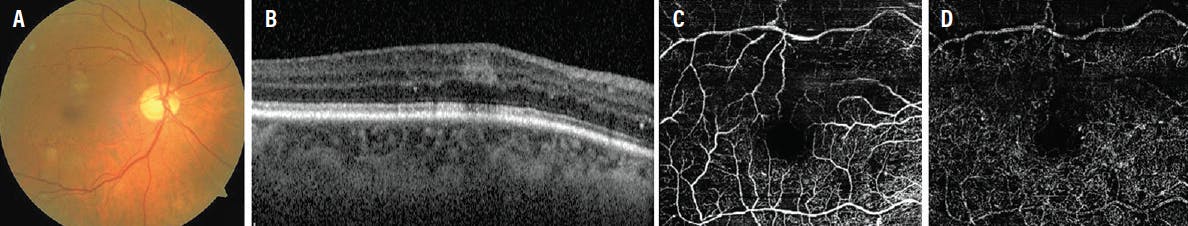

A 60-year-old woman with diabetes presented with mild blurred vision in the right eye for 3 months. Her BCVA was 20/20+ OD. Fundus examination revealed mild nonproliferative diabetic retinopathy (NPDR) without clinically significant macular edema and a grayish lesion superior to the center of the fovea (Figure 4A). OCT revealed a hyperreflective band at the level of the OPL (Figure 4B). OCTA showed an area of capillary abnormality in the DCP superior to the foveal center (Figure 4C and 4D). After 3 months, the retinal condition was stable with the persistence of PAMM.

<p>Figure 4. The fundus photo suggests diabetic retinopathy with PAMM superior to the center of the fovea (A). SD-OCT shows a hyperreflective band at the OPL (B). OCTA shows an area of capillary abnormality in the DCP superior to the foveal center (C and D).</p>

Figure 4. The fundus photo suggests diabetic retinopathy with PAMM superior to the center of the fovea (A). SD-OCT shows a hyperreflective band at the OPL (B). OCTA shows an area of capillary abnormality in the DCP superior to the foveal center (C and D).